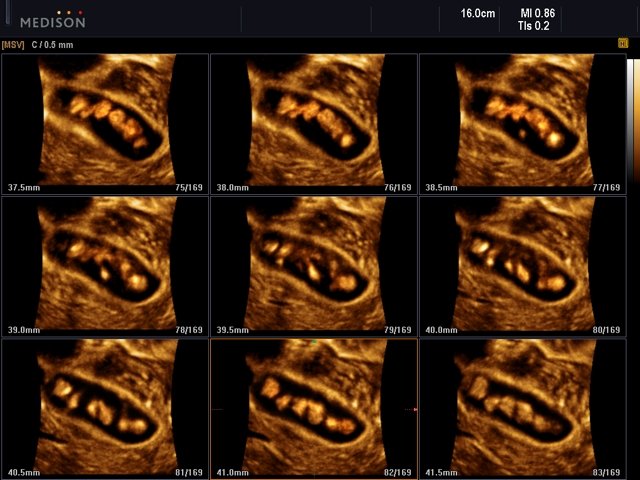

- MSV (Multi-Slice View или мультислайсинг) - возможность одновременного просмотра на экране множественных срезов, полученных при трехмерном сканировании.

- Multi Volume Slice - одновременный просмотр на экране нескольких объемных срезов трехмерного объекта исследования.